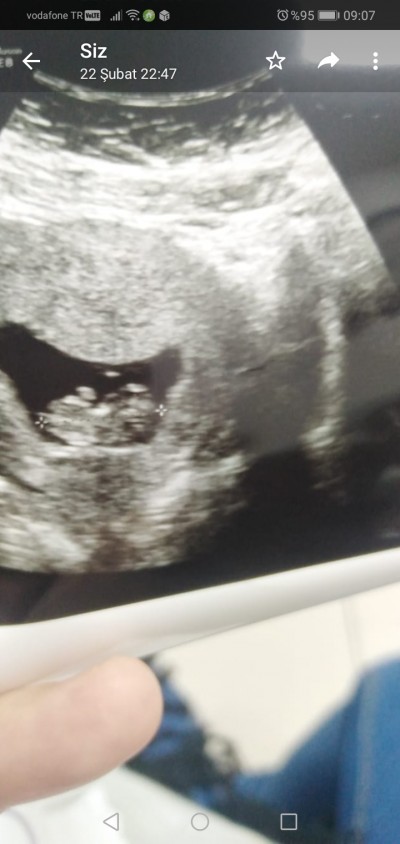

Kızlar sizce ne haftaya gel dedı 12 haftalık

Gebelik haftası 12+3